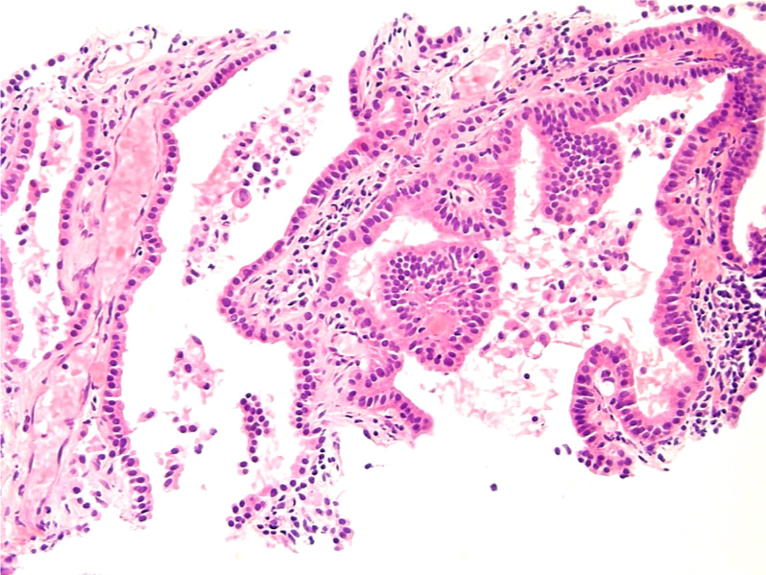

CT-guided biopsy of the lesion was again obtained. Histology results now showed papillary epithelial proliferation with papillary cores lined by cuboidal to low columnar nonciliated epithelial cells (Figure 3). There was absence of mitotic activity, and immunohistochemistry results were negative for chromogranin and synaptophysin, findings most consistent with papillary adenoma. The findings were morphologically distinct from her prior atypical carcinoid.

Figure 3. Histology results of the bilobed confluent nodule shows papillary profiles with well-formed papillary cores lined by cuboidal to low columnar nonciliated epithelial cells.